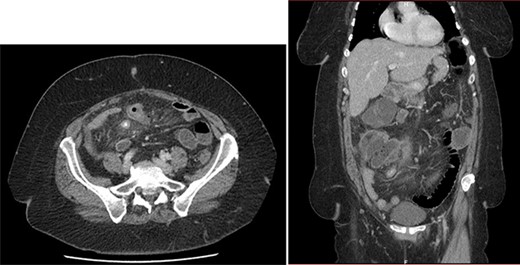

On the sixth post-operative day, the patient suddenly felt weak. She presents with pallor, hypotension and tachycardia. We noticed some blood in the left drain. We immediately started a fluid resuscitation and performed an urgent CT which showed a fresh 6-cm wide splenic sub capsular hematoma associated with a major hemoperitoneum (Fig. 2).

First, we embolized the splenic artery with coils (Fig. 3). The patient was getting well at intensive unit care, but few hours after embolization, she was shocked again.

We decided then to perform an emergency laparotomy that revealed a massive splenic hematoma and a totally burst spleen. We carried out the splenectomy and controlled the splenic vessels.